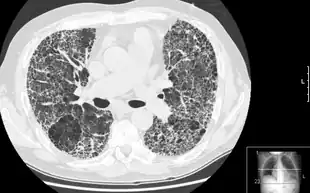

| Other names: Interstitial pulmonary fibrosis | |

| A chest X-ray demonstrating pulmonary fibrosis believed to be due to amiodarone. | |